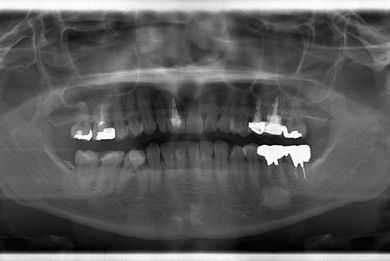

| 性別/年齢 | 女性 / 38歳 | ||||||||||||||||||||||||||||||||

| 主訴 | 右奥歯2本、インレーの相談をしたい。 | ||||||||||||||||||||||||||||||||

| 治療方針 | セラミック治療にて、審美的回復を行う。 | ||||||||||||||||||||||||||||||||

| 治療内容 | ハイブリッドセラミックインレー2本、メタルボンドセラミッククラウン2本(メタルボンド用土台2本)、オールセラミッククラウン1本(オールセラミック用土台1本) | ||||||||||||||||||||||||||||||||

| 総治療費 | 495,758円 | ||||||||||||||||||||||||||||||||

| 治療期間 | 1年6ヶ月 |